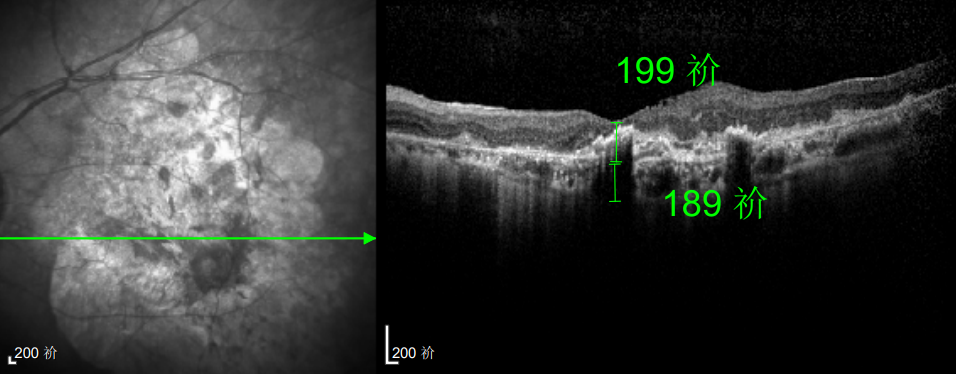

△延误复查后的左眼

这次教训让林婆婆彻底醒悟,此后她严格遵照王晓波主任的医嘱,定期随访、规范治疗,再也不敢有丝毫懈怠。虽然左眼视力最终仅恢复至0.3,但稳定的视力状态让她格外珍惜。

△规划化治疗后的左眼